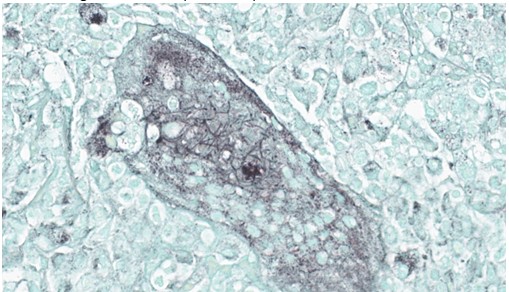

Lung, multiple sections. Within a single section of lung, approximately 75% of the bronchial, bronchiolar, and alveolar lumina contain overall large numbers of neutrophils, macrophages, large multinucleated cells, cellular debris, homogenous eosinophilic material, fibrillary eosinophilic material, and occasionally scattered erythrocytes. The multinucleated cells are often large and bizarre in appearance, some containing approximately 40 nuclei. The cytoplasm of these multinucleated cells is eosinophilic and variably granular to homogenous. A subset of these multinucleated cells contains few distinct optically clear vacuoles, while others demonstrate phagocytosis of few neutrophils. There is mild vascular congestion throughout, and there are small clusters of lymphocytes cuffing airways multifocally.Contributor's Morphologic Diagnoses:

Transmission electron microscopy provided ultrastructural evidence of bacteria within giant cells, with no viral particles identified.

The sample was immunoreactive on a polybacterial immunohistochemical assay, but negative for select gram-negative bacteria on a separate immunohistochemical assay. PCR testing for the groEL gene of mycobacteria and Nocardia spp. was positive, with subsequent sequencing identifying Nocardia spp. PCR testing for gram-negative bacteria specific 16S rRNA gene was positive for Pasteurellaceae. Immunohistochemical staining for Pasteurella multocida was negative. PCR testing for gram-positive bacteria specific 16S rRNA gene was indeterminate. Repeat acid fast staining (Fite’s stain) identified long filamentous rods within the giant cells.

Our fourth conference this year was moderated by the esteemed Dr. Thomas Cecere from Virgina Tech. The JPC team was thrilled to have him back for the second year in a row. This first case provided a great discussion on diagnostic workups and the processes that the pathologist should consider when choosing next steps in a case. Here, the lungs were “chock-a-block” full with histiocytic and neutrophilic inflammation with numerous giant cells that one participant remarked as having “a million nuclei.” These were some of the most impressive giant cells that many participants had seen. The bacteria were very difficult to see on the H&E, but the pattern of inflammation and presence of such robust giant cells should clue one into the presence of infectious organisms. As such, next steps should include a full gamut of routine infectious organism stains, including gram stains, acid fast stains, and fungal stains (GMS, PAS). Given that these were performed by the contributor, only confirmatory GMS and Fite-Faraco (FF) stains were performed in house, which revealed weakly acid-fast, GMS-positive organisms within multinucleated giant cells. This is consistent with the Nocardia spp. that were identified by the contributor. Those “chef’s kiss” multinucleated giant cells, though, deserve some recognition here.The multinucleated giant cell macrophage is a truly remarkable physiologic phenomenon. How they are formed is poorly understood. The current understanding is that macrophages need to be present in chronic inflammation, where they are constantly exposed to pro-inflammatory cytokines, such as IFN-γ, IL-3, IL-4, IL-13, and GM-CSF, as well as pathogen-associated molecular patterns (PAMPs) and other mediators of inflammation.1 A common setting in which these “ingredients” are found is in fungal infections or when dealing with foreign bodies, both of which can sometimes be too large for inflammatory cells to phagocytose and handle on their own. In this environment, macrophages will be in close association with one another and will begin to express molecules on their cell surface that enable fusion with one another, including dendritic cell-specific transmembrane protein (DC-STAMP; major driver of fusion), β1 and β2 integrins, CD44 (hyaluronic acid receptor), CD47 (integrin-associated protein), macrophage fusion protein receptor (MFPR), fusion regulatory protein (FRP-1, also known as CD98), and P2X7 (an ATP-activated ion channel that results in pore formation).1